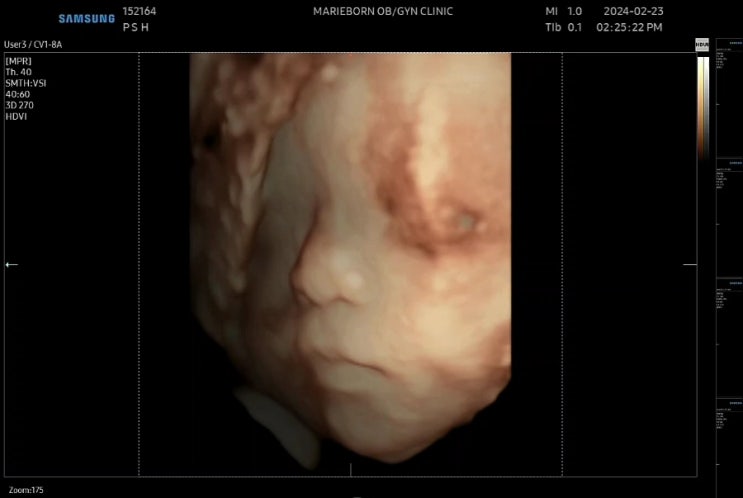

[임신 27,28주차] 3D입체초음파, 임신성당뇨검사, 진료결과

안녕하세요! 한방이맘이에요! 20주차의 마지막 검진이면서 하이라이트인 27주차 입체초음파를 보고왔어요~~...